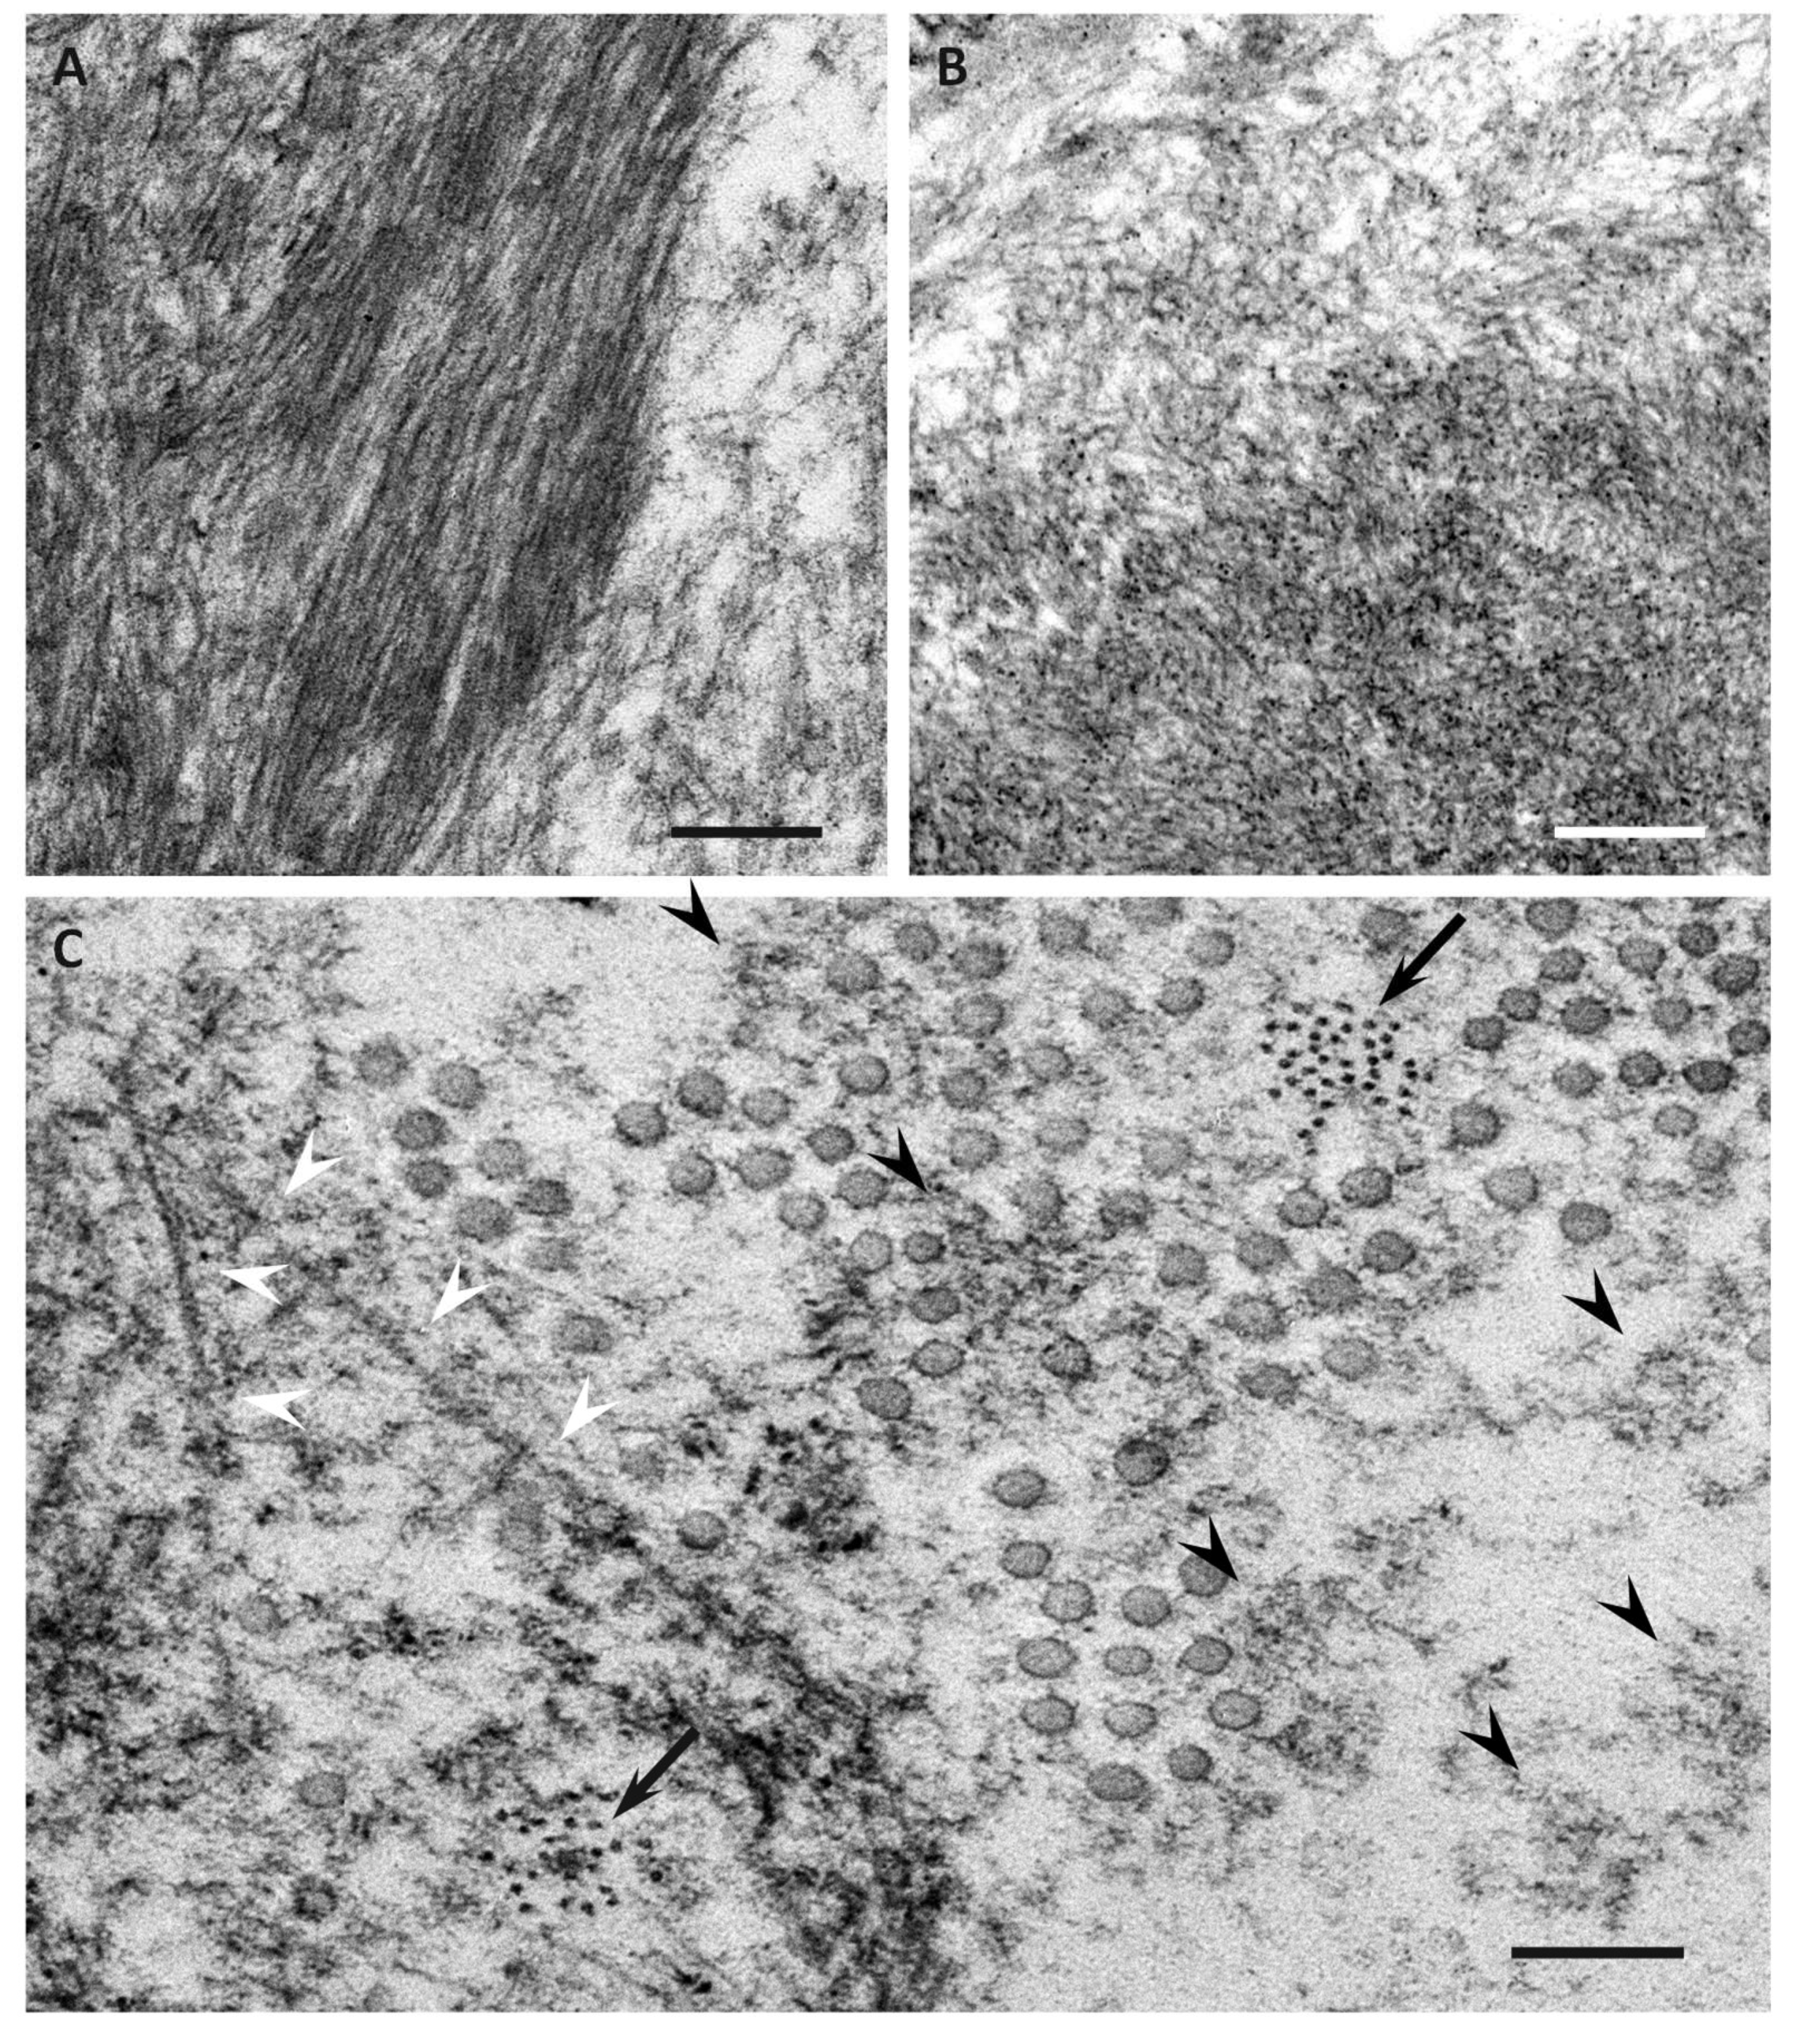

Electron microscopic studies of nerve biopsy specimens from patients with ATTRv amyloidosis have shown that amyloid fibrils were formed among amorphous electron-dense materials located in extracellular spaces of the endoneurium [56]. Amorphous electron-dense materials tend to be observed around microvessels and the subperineurial space. Among these amorphous materials, dotty or fine fibrillar structures are frequently observed (Figure 2C). The dotty structures seem to be the core of amyloid fibrils because slightly elongated fibrillar structures with a thickness similar to the diameter of these dots are frequently found [56]. The mature long fibers usually occupy the central part of the large aggregations of amyloid fibrils, while the amorphous materials, dotty structures, and short amyloid fibrils tend to be present at the periphery of the aggregates of amyloid fibrils. During the process of amyloid fibril maturation, amyloid fibrils seem to pull surrounding tissues [56]. This traction of neighboring tissues seems to be conspicuous in cases with long and thick amyloid fibrils, such as early-onset Val30Met cases in endemic foci (Figure 3A) [51,56]. By contrast, amyloid fibril maturation seems to have a smaller influence on neighboring tissues in cases with short and fine amyloid fibrils, such as late-onset Val30Met cases in nonendemic areas (Figure 3B) [51,56].

Figure 3.

Impact of amyloid fibril formation on neighboring tissues in early-onset ATTR Val30Met amyloidosis patients from endemic foci (A) and late-onset ATTR Val30Met amyloidosis patients from nonendemic areas (B). Cross sections of sural nerve biopsy specimens. Uranyl acetate and lead citrate staining. During the process of amyloid fibril maturation, amyloid fibrils seem to pull surrounding tissues. This traction of neighboring tissues seems to be conspicuous in patients with long and thick amyloid fibrils, such as early-onset Val30Met patients from endemic foci (A). By contrast, the impact of amyloid fibril maturation on neighboring tissues seems to be less in patients with short and fine amyloid fibrils, such as late-onset Val30Met patients from nonendemic areas (B). The stretched basement membrane in (A) is indicated by arrowheads. An unmyelinated fiber in (B) is indicated by an asterisk. Scale bars = 0.5 μm.